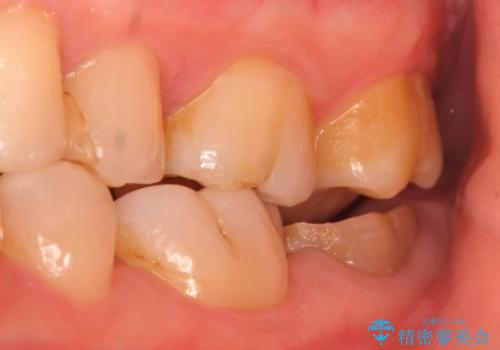

診査の結果根尖病変を認めたため再根管治療を行った後に、被せ物を入れるスペースを作るため歯冠延長術を行いました。

歯冠延長術について

歯冠長延長術とは歯肉弁根尖側移動術とも言い、歯の高さが低くクラウン(被せ物)による治療が難しい場合に、歯茎を歯根方向に下げることで歯の高さを確保する手術です。歯の高さが十分にあることで、外れにくいしっかりとしたクラウンを被せることができます。

今回用いたオールセラミッククラウンはジルコニアフレームという白い素材の上にセラミックを盛っているため、審美性が非常に高いのが特徴です。

また、ジルコニアは人工ダイヤモンドの材料にも使われているほど高い強度を持っており、そのためオールセラミッククラウンは審美性だけでなく、奥歯やブリッジの補綴も可能とするクラウンです。